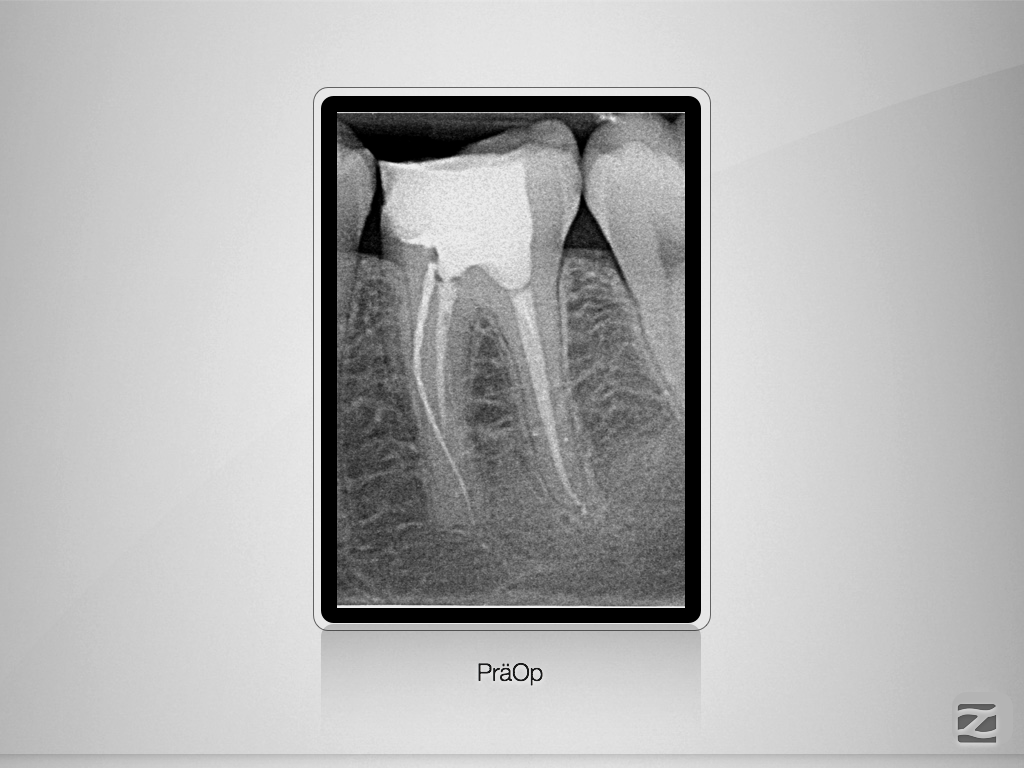

Fraktur auf voller Arbeitslänge